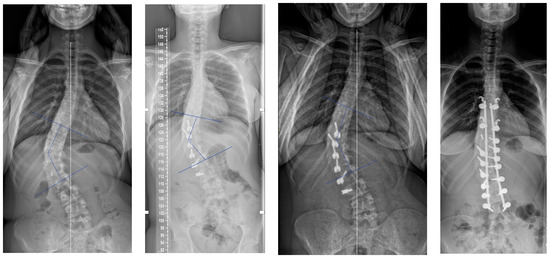

Posterior Vertebral Body Tethering: A Preliminary Study of a New Technique to Correct Lenke 5C Lumbar Curves in Adolescent Idiopathic Scoliosis

2.2. Surgical Technique

3. Results